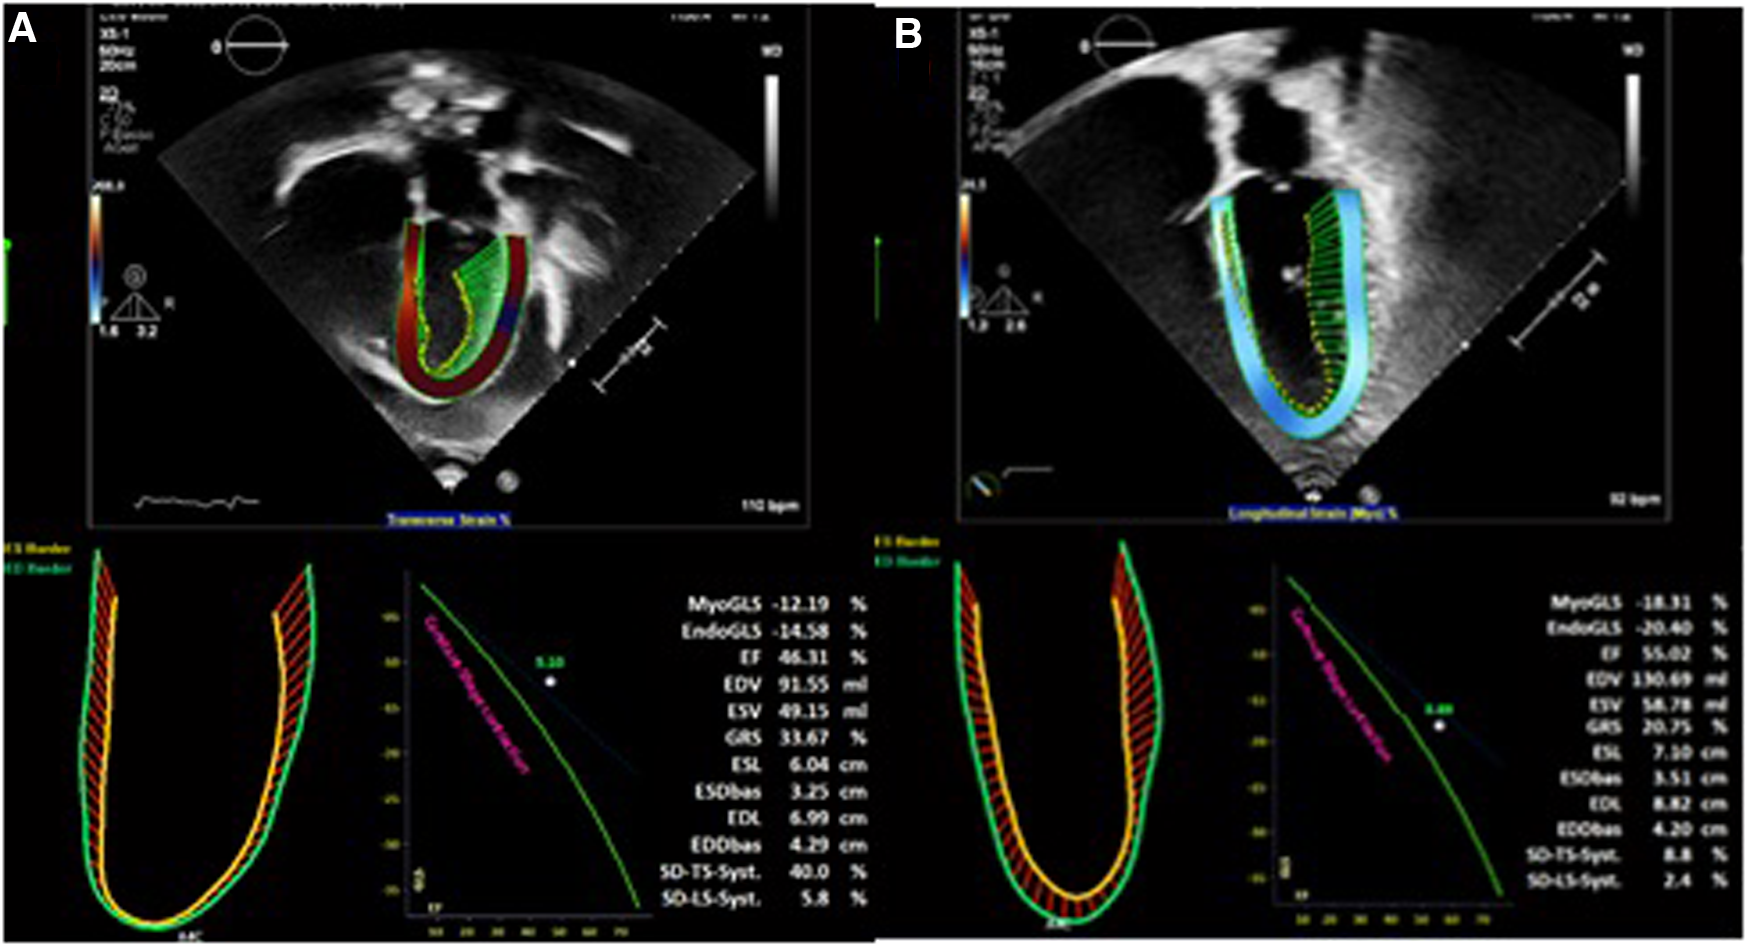

An 18-year-old male presented to our hospital with worsening fatigue. His past medical history was negative for any pathologies. He progressively developed pericardial and pleural effusions; subsequently, polyserositis was diagnosed. Therapy with ibuprofen, corticosteroids, and colchicine was started without any significant improvements; therefore, the patient was started on anakinra, which also did not contribute to any substantial improvement in the condition. Broad serological tests of infectious and collagen diseases were performed, including hepatitis viruses, toxoplasma, mycoplasma, venereal disease research laboratory (VDRL), cytomegalovirus, human herpes 6 (HH6), human herpes 8 (HH8), Epstein–Barr virus (EBV), human immunodeficiency virus, Coxsackie viruses, and antinuclear and rheumatic factors. All results were negative except for immunoglobulin M (IgM) antiviral capsid antigen (VCA) for EBV. Our patient was not related to a tuberculosis-endemic area; however, PCR for tuberculosis was performed in blood samples, sputum, and pericardial fluid, and the results were negative. Blood tests were found weakly positive for IgM VCA, and the extended autoantibody panel (ANA, ENA, ANCA, ASCA, and FR) was negative. Screening for celiac disease was also negative, and thyroid function tests were within normal limits. We also found tamponade pericardial effusion. It was, therefore, necessary to perform the first pericardiocentesis. Pericardial fluid was negative for malignant cells yet positive for inflammatory cells, and the polymerase chain reaction (PCR) test was positive only for EBV. Examinations for all other infectious agents (HH6, HH8, TB, CMV, Enterovirus) were negative. A chest computed tomography (CT) scan was performed, identifying lymph node conglobate in the right lung hilum, bilaterally in the supraclavicular and mesenteric areas. A bone marrow biopsy was also performed and was negative for lymphoproliferative disease. The transthoracic echocardiography showed moderate dysfunction of the left ventricle (LV) (with an ejection fraction of 46%), severe desynchrony of the ventricular septum, a global longitudinal strain (GLS) of −12.9%, the right ventricle (RV) with a normal function, and no significant regurgitation of the atrioventricular valve (Figure 1A). Cardiac magnetic resonance imaging (MRI) showed mild global biventricular systolic dysfunction [left ventricular ejection fraction (LVEF) 46%, right ventricular ejection fraction (RVEF) 47%] and circumferential pericardial effusion (maximum thickness 15–16 mm); right pleural effusion was identified (maximum thickness 3.5 cm), and there were no signs of pericardial constriction. Several days after pericardiocentesis with the extraction of about 400 ccs of blood serum liquid, a positron emission tomography (PET) CT scan and whole-body MRI scan were performed to exclude any underlying neoplastic processes. Once clinical and hemodynamic improvements were achieved, the patient was discharged with indications for close follow-up. One and two months after the patient was discharged, the echocardiography showed a stable condition with the persistence of a slight amount of pericardial effusion in the apical site and along the lateral wall of the left ventricle. After 3 months and mainly after 4 months, the echocardiogram showed worsening of the condition toward effusive-constrictive pericarditis, with enlargement of atrial sizes, alterations of diastolic function, dilation of the hepatic veins and inferior vena cava, and thickening and hyper-reflection of the pericardial leaflets. Abdominal ultrasound revealed effusion in all quadrants. A cardiac MRI was performed also 6 months after the first one and confirmed constriction with diffuse fibrotic thickening of the pericardial sac and signs of ventricular interdependence evident in the dynamic sequences (flattening of the interventricular septum in maximal inspiration), suggestive of constrictive physiology (Figure 2). The persistence of pericardial effusion along the mid-apical lateral wall of the LV was also identified (maximal thickness 10 mm). Finally, to confirm a restrictive picture, cardiac catheterization was performed, highlighting multiple elements suggestive of constrictive physiology with equalization of the diastolic filling pressure of the cardiac chambers and left and right ventricular diastolic “dip and plateau” appearance. Marked ventricular interdependence during the respiratory cycle and post-capillary pulmonary hypertension was noted. A diagnosis of constrictive effusive pericarditis was made (Figure 3, Table 1). The pre-operative cardiac catheterization showed pressure in the pulmonary artery of 35/21–25 mmHg and pulmonary wedge pressure of 22 mmHg (Table 1). At this point, the patient underwent anterior and posterior pericardiectomy surgery with preservation of the phrenic nerves, a procedure performed in normothermic cardiopulmonary bypass with a beating heart (Figure 4). Both intraoperative and postoperative periods were uncomplicated. The histological sample confirmed marked fibrous thickening with extreme rarefaction and fragmentation of the elastic fibers and mild lymphoplasmacytic inflammatory infiltrate (CD3+, CD20+, and CD38+), as well as neutrophilic granulocytes with numerous hemosiderin deposits and neovascularization. The in situ hybridization investigation with the Epstein–Barr-encoded small RNA (EBER) probe for the detection of EBV was positive, confirming the clinical suspicion of chronic pericarditis caused by EBV. Transesophageal echocardiography performed immediately after surgical excision of the fibrous pericardium showed complete recovery and normalization of ventricular septal motion. A few weeks after surgery, abdominal ultrasound showed a complete absence of peritoneal effusion. One week after surgery, transthoracic echocardiography was repeated and showed normalization of left ventricular function (3D ejection fraction 55%), and the GLS improved (−18.3%) (Figure 1B). The follow-up at 3, 6, and 12 months revealed no signs and symptoms related to diastolic heart failure, and echocardiogram findings were normal.

Figure 1. (A) Transthoracic echocardiography before cardiac surgery. (B) Transthoracic echocardiography after cardiac surgery.